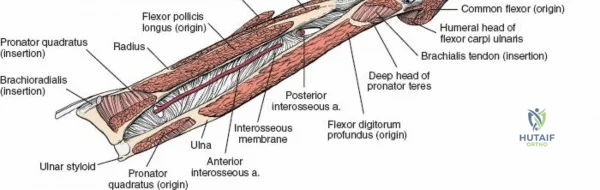

The Internervous Planes of the Forearm

The anterior approach to the radius is an elegant example of utilizing true internervous planes to achieve deep exposure without denervating musculature. Distally, the internervous plane lies between the brachioradialis muscle (innervated by the radial nerve) and the flexor carpi radialis muscle (innervated by the median nerve). Proximally, the plane transitions to lie between the brachioradialis (radial nerve) and the pronator teres muscle (median nerve). Exploiting this plane allows the surgeon to mobilize the entire lateral muscular compartment (the "mobile wad" comprising the brachioradialis, extensor carpi radialis longus, and extensor carpi radialis brevis) away from the anterior flexor compartment.

Vascular Anatomy and the Recurrent Radial Leash

The radial artery runs distally through the forearm, initially lying deep to the brachioradialis muscle before becoming more superficial in the distal third. Just distal to the elbow joint, the radial artery gives off a complex network of vessels known as the recurrent radial artery leash (the "leash of Henry"). These vessels branch laterally to supply the brachioradialis and the mobile wad. To successfully mobilize the brachioradialis laterally and access the proximal radius, this entire leash of vessels must be meticulously isolated, ligated, and divided. Failure to do so will tether the brachioradialis, prevent adequate exposure, and risk severe postoperative hematoma from avulsed vessels.

Managing the Radial Artery and Recurrent Leash

As the brachioradialis is retracted laterally, the radial artery and its venae comitantes are exposed lying deep in the middle part of the forearm, closely related to the medial edge of the wound. Begin dissection distally and work proximally. Just below the elbow joint, the radial artery gives off the recurrent radial artery and a leash of muscular branches that dive laterally into the brachioradialis.

This leash must be meticulously managed. Take time to isolate, ligate, and divide these vessels. Do not attempt to use electrocautery alone on the larger branches, and absolutely avoid blunt avulsion. Avulsion of these vessels from the main radial artery is a potent cause of difficult-to-control intraoperative bleeding and severe postoperative hematoma. Once the leash is divided, the brachioradialis can be fully mobilized laterally, exposing the deep muscular layer.

Exposing the proximal third of the radius requires extreme vigilance due to the proximity of the posterior interosseous nerve. The key anatomical landmark here is the insertion of the biceps tendon. Follow the biceps tendon distally to its insertion on the bicipital tuberosity of the radius. A small bursa lies just lateral to the tendon; incise this bursa to gain initial access to the proximal radial shaft. Because the radial artery lies superficial and medial to the tendon at this level, all deep dissection must remain strictly lateral to the biceps tendon.

The proximal radius is draped by the supinator muscle. The PIN passes directly through the belly of the supinator. To protect the nerve, the forearm must be fully supinated. Supination dynamically rotates the radius, carrying the insertion of the supinator anteriorly and simultaneously displacing the PIN laterally and posteriorly, safely away from the surgical field.

With the forearm fully supinated, identify the broad insertion of the supinator on the anterior aspect of the radius. Incise the supinator directly along the line of its insertion onto the bone. It is critical to detach the muscle by dividing its insertion sharply at the bone, rather than splitting the muscle belly, which would risk cutting the PIN.

Proceed with strict subperiosteal dissection, elevating the supinator laterally off the bone. This is one of the rare instances in orthopedic surgery where the safety gained by staying in a subperiosteal plane completely outweighs the theoretical vascular damage to the bone caused by periosteal stripping. The elevated supinator muscle belly now acts as a protective cushion for the PIN.